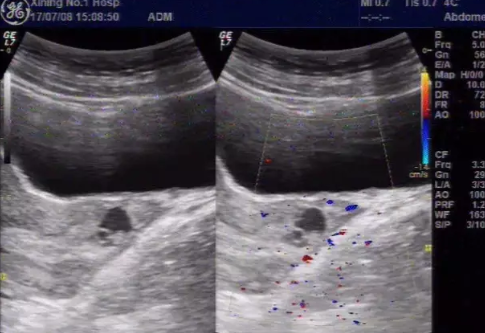

超聲檢查顯示,宮頸管內(nèi)妊娠,子宮腔內(nèi)無異物。多普勒超聲檢查能夠輔助區(qū)分宮頸妊娠和子宮內(nèi)妊娠。組織學(xué)檢查證實,宮頸基質(zhì)內(nèi)存在絨毛。宮頸妊娠最有效的治療方案尚不明確。但是對于80-90%早期宮頸妊娠患者,肌內(nèi)注射單或多劑量甲氨蝶呤是有效的。

臨床上診斷宮頸妊娠主要依靠經(jīng)陰道的超聲檢查:

在宮頸內(nèi)發(fā)現(xiàn)胎囊或胎盤

子宮內(nèi)膜形態(tài)正常

子宮沙漏樣外觀和子宮頸管膨大